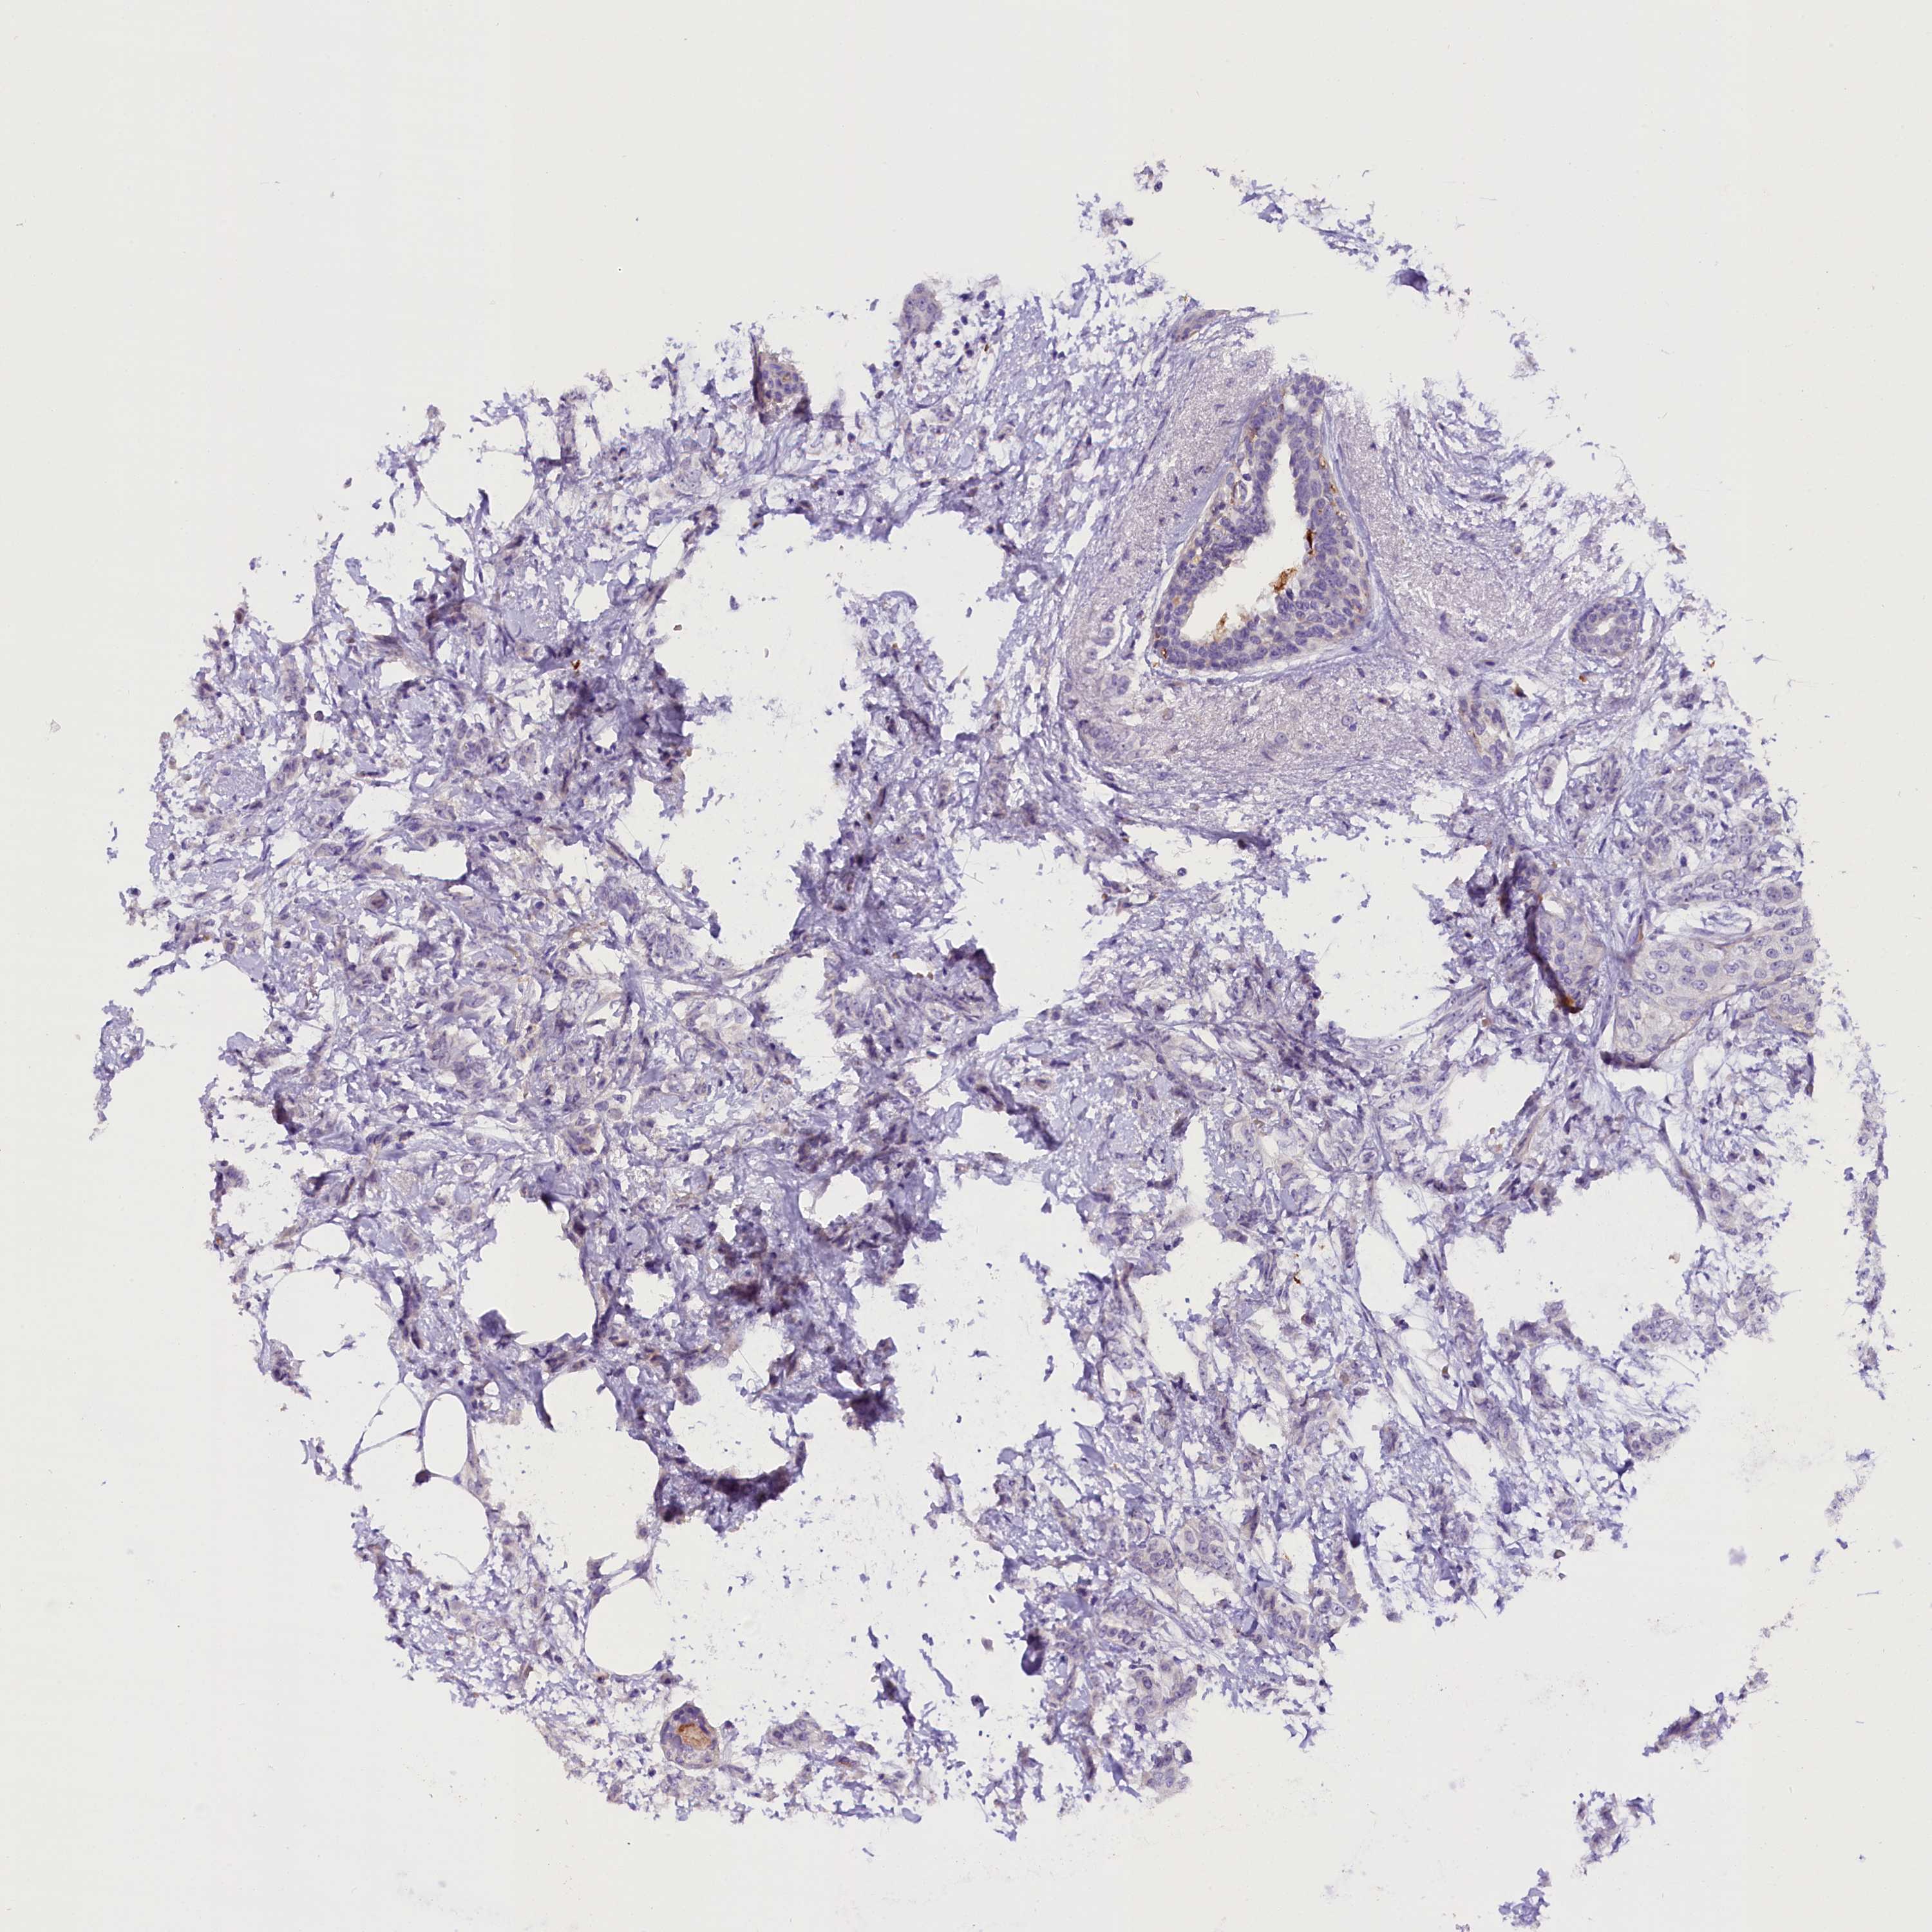

CANCER BREAST CANCER Show tissue menu

BRCA TCGA BRCA VALIDATION PROTEIN EXPRESSION

ANTIBODIES

AND

VALIDATION